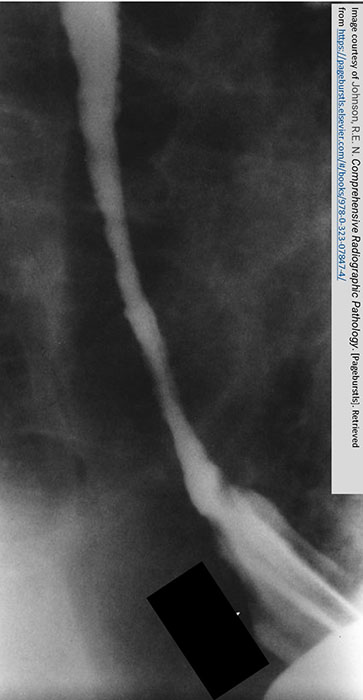

What is the radiographic appearance of the infiltrating type of esophageal carcinoma?

Irregular narrowing, mucosal destruction, esophageal dilation above lesion.

What is 'shelving' in esophageal carcinoma?

Sharp, shelf-like demarcation between normal and diseased esophagus (classic infiltrative sign).